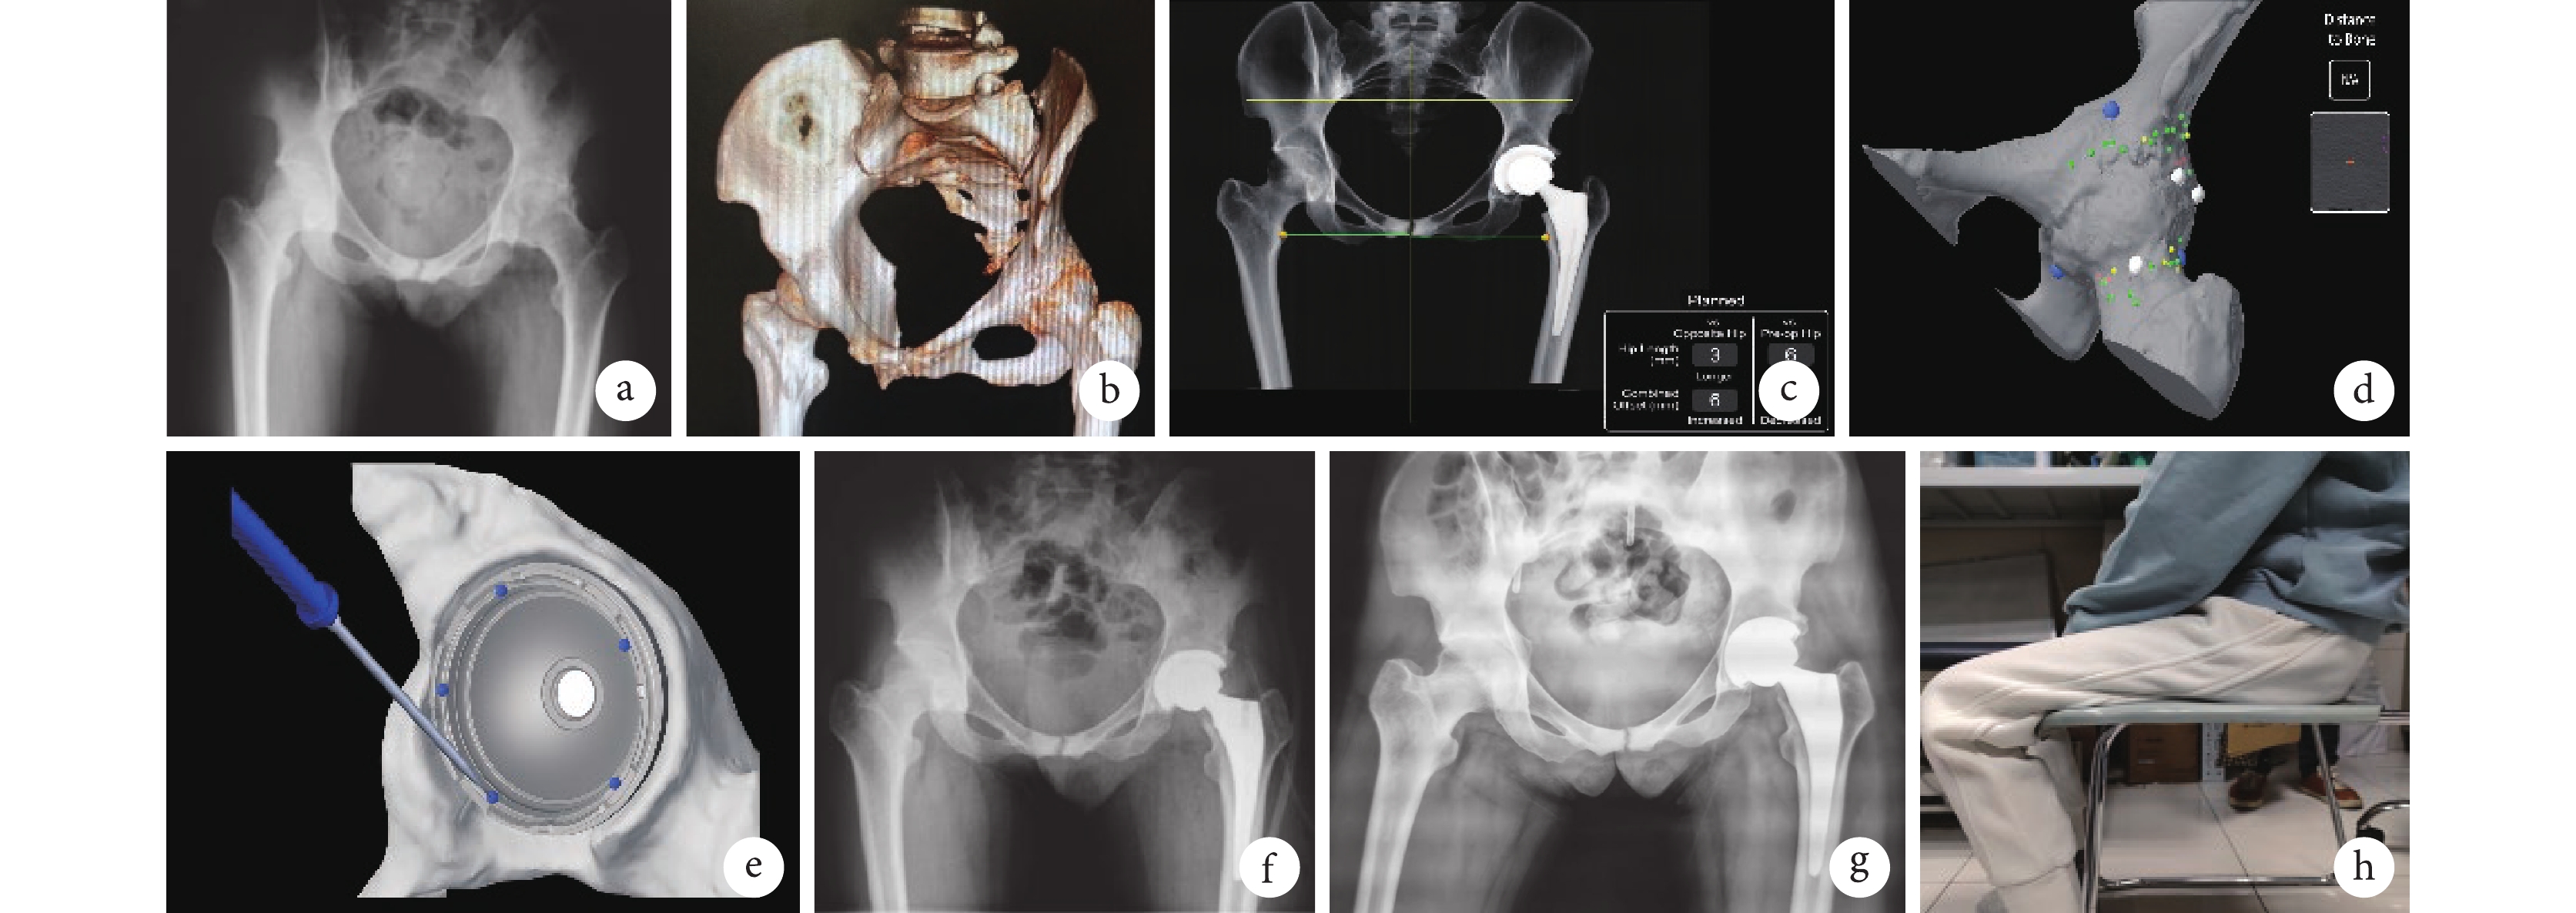

a. 術前骨盆X線片;b. 術前髖關節CT三維重建;c. 術前假體規劃;d. 術中髖關節位置注冊和驗證;e. 術中確認髖臼假體角度;f. 術后2 d骨盆X線片;g. 術后6個月雙髖關節X線片;h. 術后6個月坐姿

患者 女,35歲。因“左髖關節疼痛伴活動受限6年,加重伴僵直1年”入院。既往確診“強直性脊柱炎”10余年。查體:左髖輕度腫脹,伸直位強直,無活動度,左髖軸向叩擊痛陰性,腹股溝區壓痛陰性;右髖無明顯陽性體征;雙下肢末梢血運、感覺、肌力及肌張力無明顯異常。實驗室檢查:紅細胞沉降率29 mm/1 h,C反應蛋白6.3 mg/L。影像學檢查:雙髖關節正位X線片示左髖關節間隙消失,左側股骨頭形態異常,左髖關節骨性融合(圖1a);髖關節+股骨CT平掃及三維重建示左髖關節骨性融合,雙側骶髂關節炎(圖1b)。診斷:強直性脊柱炎骨性融合髖(以下簡稱“骨性強直髖”),擬行左髖人工全髖關節置換術(total hip arthroplasty,THA)。左髖術前疼痛視覺模擬評分(VAS)為3分,Harris評分為58分,牛津大學髖關節評分(OHS)為43分。

采用MAKO機器臂輔助THA系統(史塞克公司,美國)進行手術。術前行機器人髖關節CT建模,根據患者骨質情況,規劃假體型號、位置、相關角度、高度和深度等參數(圖1c)。全身麻醉后取仰臥位,于對側髂前上棘上方平行置入3枚螺釘安裝定位導航器。以髂前上棘下方4 cm為中心,平行于腹股溝皮紋作“比基尼”切口,暴露闊筋膜張肌肌膜;在髂前上棘與髕骨外緣連線向外2 cm縱形切開。由闊筋膜張肌與縫匠肌間隙打開深層肌膜,結扎旋股外側動脈分支血管。分離大轉子上方臀中肌與關節囊間隙暴露外上方關節囊后,切開關節囊充分暴露髖關節。髖臼外上緣和股骨大轉子處各置入check point定位螺釘,整體注冊已融合髖關節數據(圖1d),采用“兩刀法”將股骨頸原位截斷,外旋股骨,切除內側髖關節囊。在機器臂輔助下選用術前規劃的髖臼銼打磨髖臼至位置合適后,安裝對應的生物型髖臼假體,驗證髖臼安裝角度無誤后置入對應陶瓷內襯(圖1e)。骨刀清除髖臼周圍骨贅后松解股骨后外側關節囊;后伸、外旋髖關節充分暴露股骨近端,擴髓至合適大小后安裝對應生物型股骨假體;選取合適的股骨頭假體試頭后,復位檢查關節活動度及穩定性可,更換對應陶瓷股骨頭假體。沖洗切口,放置引流,逐層縫合,敷料覆蓋。

術后常規抗凝、抗感染、多模式鎮痛治療。術后體位無特殊要求,第1天在醫生指導下用助行器行走,并輔以踝泵運動和股四頭肌肌力練習;早期在疼痛耐受下做髖關節屈伸練習;6周改用單拐或手杖輔助行走,3個月開始無輔助行走。術后未出現切口感染、下肢深靜脈血栓形成和假體松動等并發癥。術后2 d X線片示髖臼外展40°、前傾15°,下肢長度較健側增加3 mm,聯合偏心距與健側相差6 mm(圖1f)。術后6個月隨訪時左髖輕微疼痛,VAS評分1分,髖關節屈伸活動度0°~90°、內旋15°、外旋20°、內收10°、外展30°;切口瘢痕反應輕(圖1g),患髖可滿足坐凳子等日常生活需要(圖1h);Harris評分85分,OHS評分19分,均較術前明顯改善。